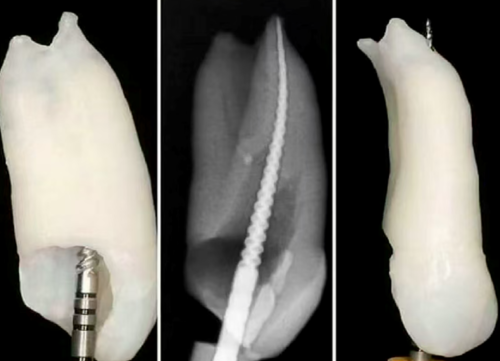

根管治疗是牙体牙髓病学中一项重要的治疗手段,旨在通过清除感染、封闭根管系统,保留患牙的功能。然而,根管治疗的成功与否,往往取决于治疗的第一步——冠方入路与髓腔预备。如果第一步操作不当,可能会导致治疗失败,甚至需要二次治疗。因此,掌握髓腔入路和冠部预备的内容、原则及操作技巧,是确保根管治疗成功的基础。